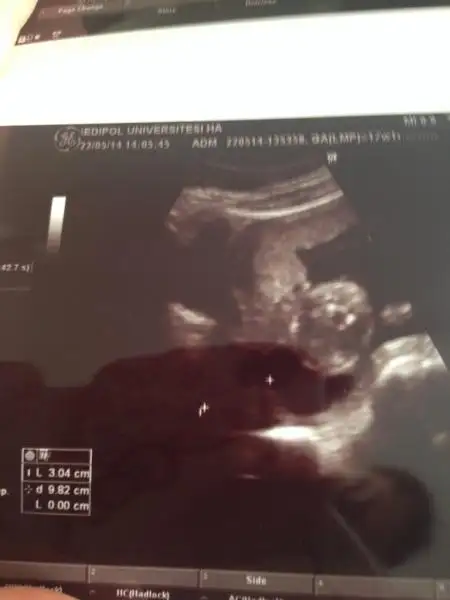

Bizimkini de tahmin edinn noluurrr :) çok merak ediyoruz ultrason 12+3 de çekildi.Eki Görüntüle 1127216

12+5 te gidicez bide o zaman resim atarim burda net degilse :)